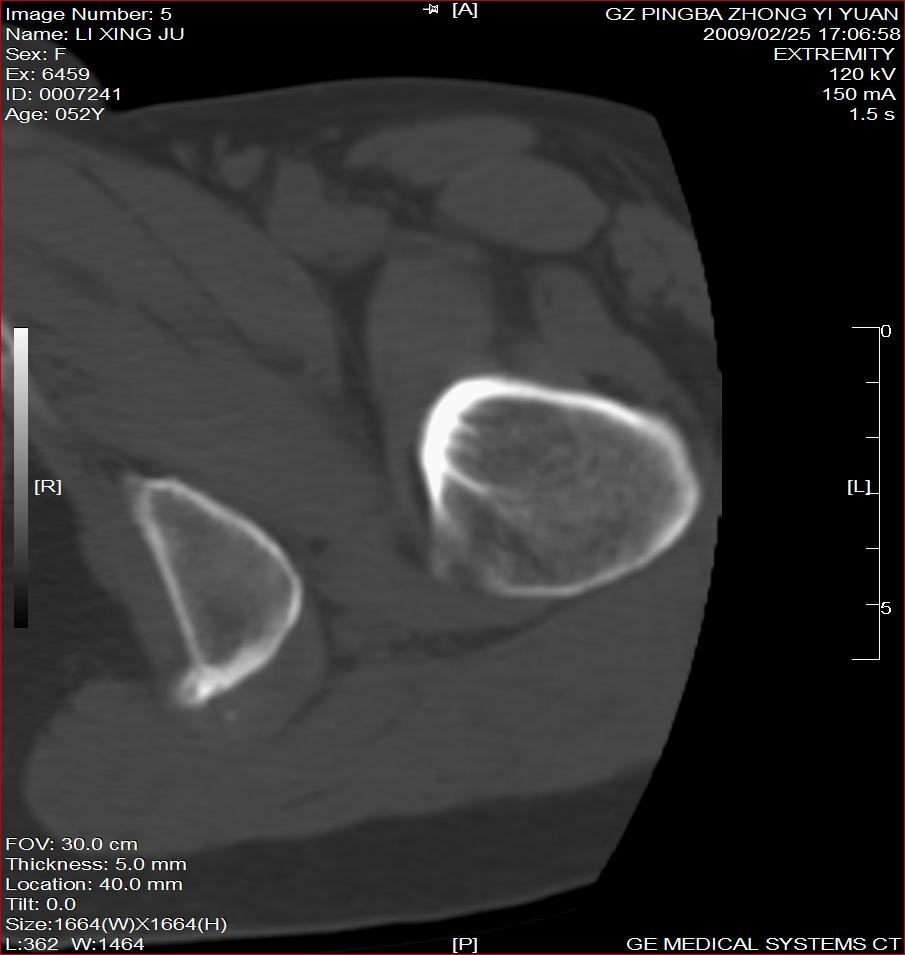

标题: CT18521:左大腿疼痛不适1+月 [打印本页]

标题: CT18521:左大腿疼痛不适1+月

考虑-----股骨骨化性纤维瘤可能性大,不除外---局限性骨纤

考虑:左股骨骨化性纤维瘤

考虑 左股骨骨化性纤维瘤。

考虑:左股骨骨化性纤维瘤。